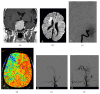

Occlusion of the intracranial internal carotid artery (ICA) by a pituitary adenoma with resulting cerebral ischemia is a very rare but devastating occurrence. The authors present a case in which a condition of symptomatic ICA occlusion due to a giant pituitary adenoma was successfully treated using a preliminary extraintracranial bypass as a "bridge" to the tumor removal. A 52-year-old patient presented with a minor stroke followed by pressure-dependent transient ischemic attacks consistent with a condition of hypoperfusion. MR imaging and a digital subtraction angiography revealed a pituitary adenoma occluding the ICA on the right side. He underwent a superficial temporal artery to middle cerebral artery (STA-MCA) bypass with the aim of revascularizing the ischemic hemisphere and reducing the risk of perioperative stroke or stroke evolution. The patient was subsequently operated on to remove the adenoma through a transsphenoidal approach. The postoperative course was uneventful and the patient has suffered no further ischemic events. When there are no emergency indications to decompress the optical pathways but the patient is at risk of impending stroke because of ICA occlusion, a two-step strategy consisting of a bypass and subsequent removal of the pituitary adenoma may be a valuable option.